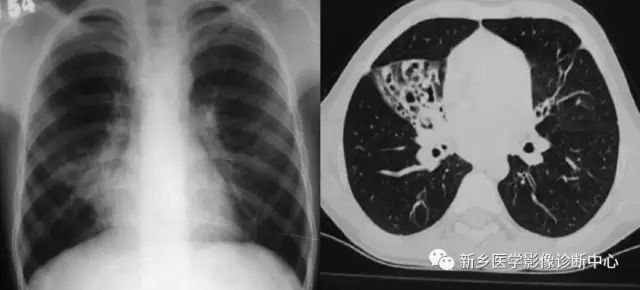

CT表现:

右中叶支气管壁增厚,管腔狭窄或支气管开口截断等。

右中叶体积缩小,其内可见斑片实变,支气管扭曲扩张等。

不同原因引起的综合症会有相应的特殊征象。